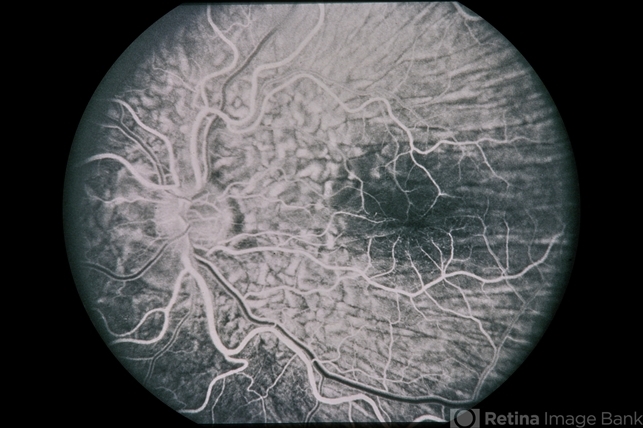

Hypotony from OverFiltration

45-year-old Hispanic male with hypotony from over-filtration.